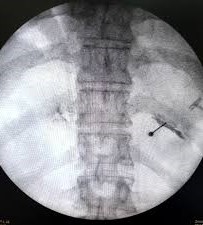

- Φαρμακευτικός αποκλεισμός μεσοπλεύριων νεύρων με έγχυση τοπικού αναισθητικού και στεροειδούς

- Νευρόλυση με χρήση ραδιοσυχνοτήτων

- Νευρόλυση με χρήση κρυοπηξίας

- Εμφύτευση ηλεκτροδίου περιφερικής νευρικής διέγερσης